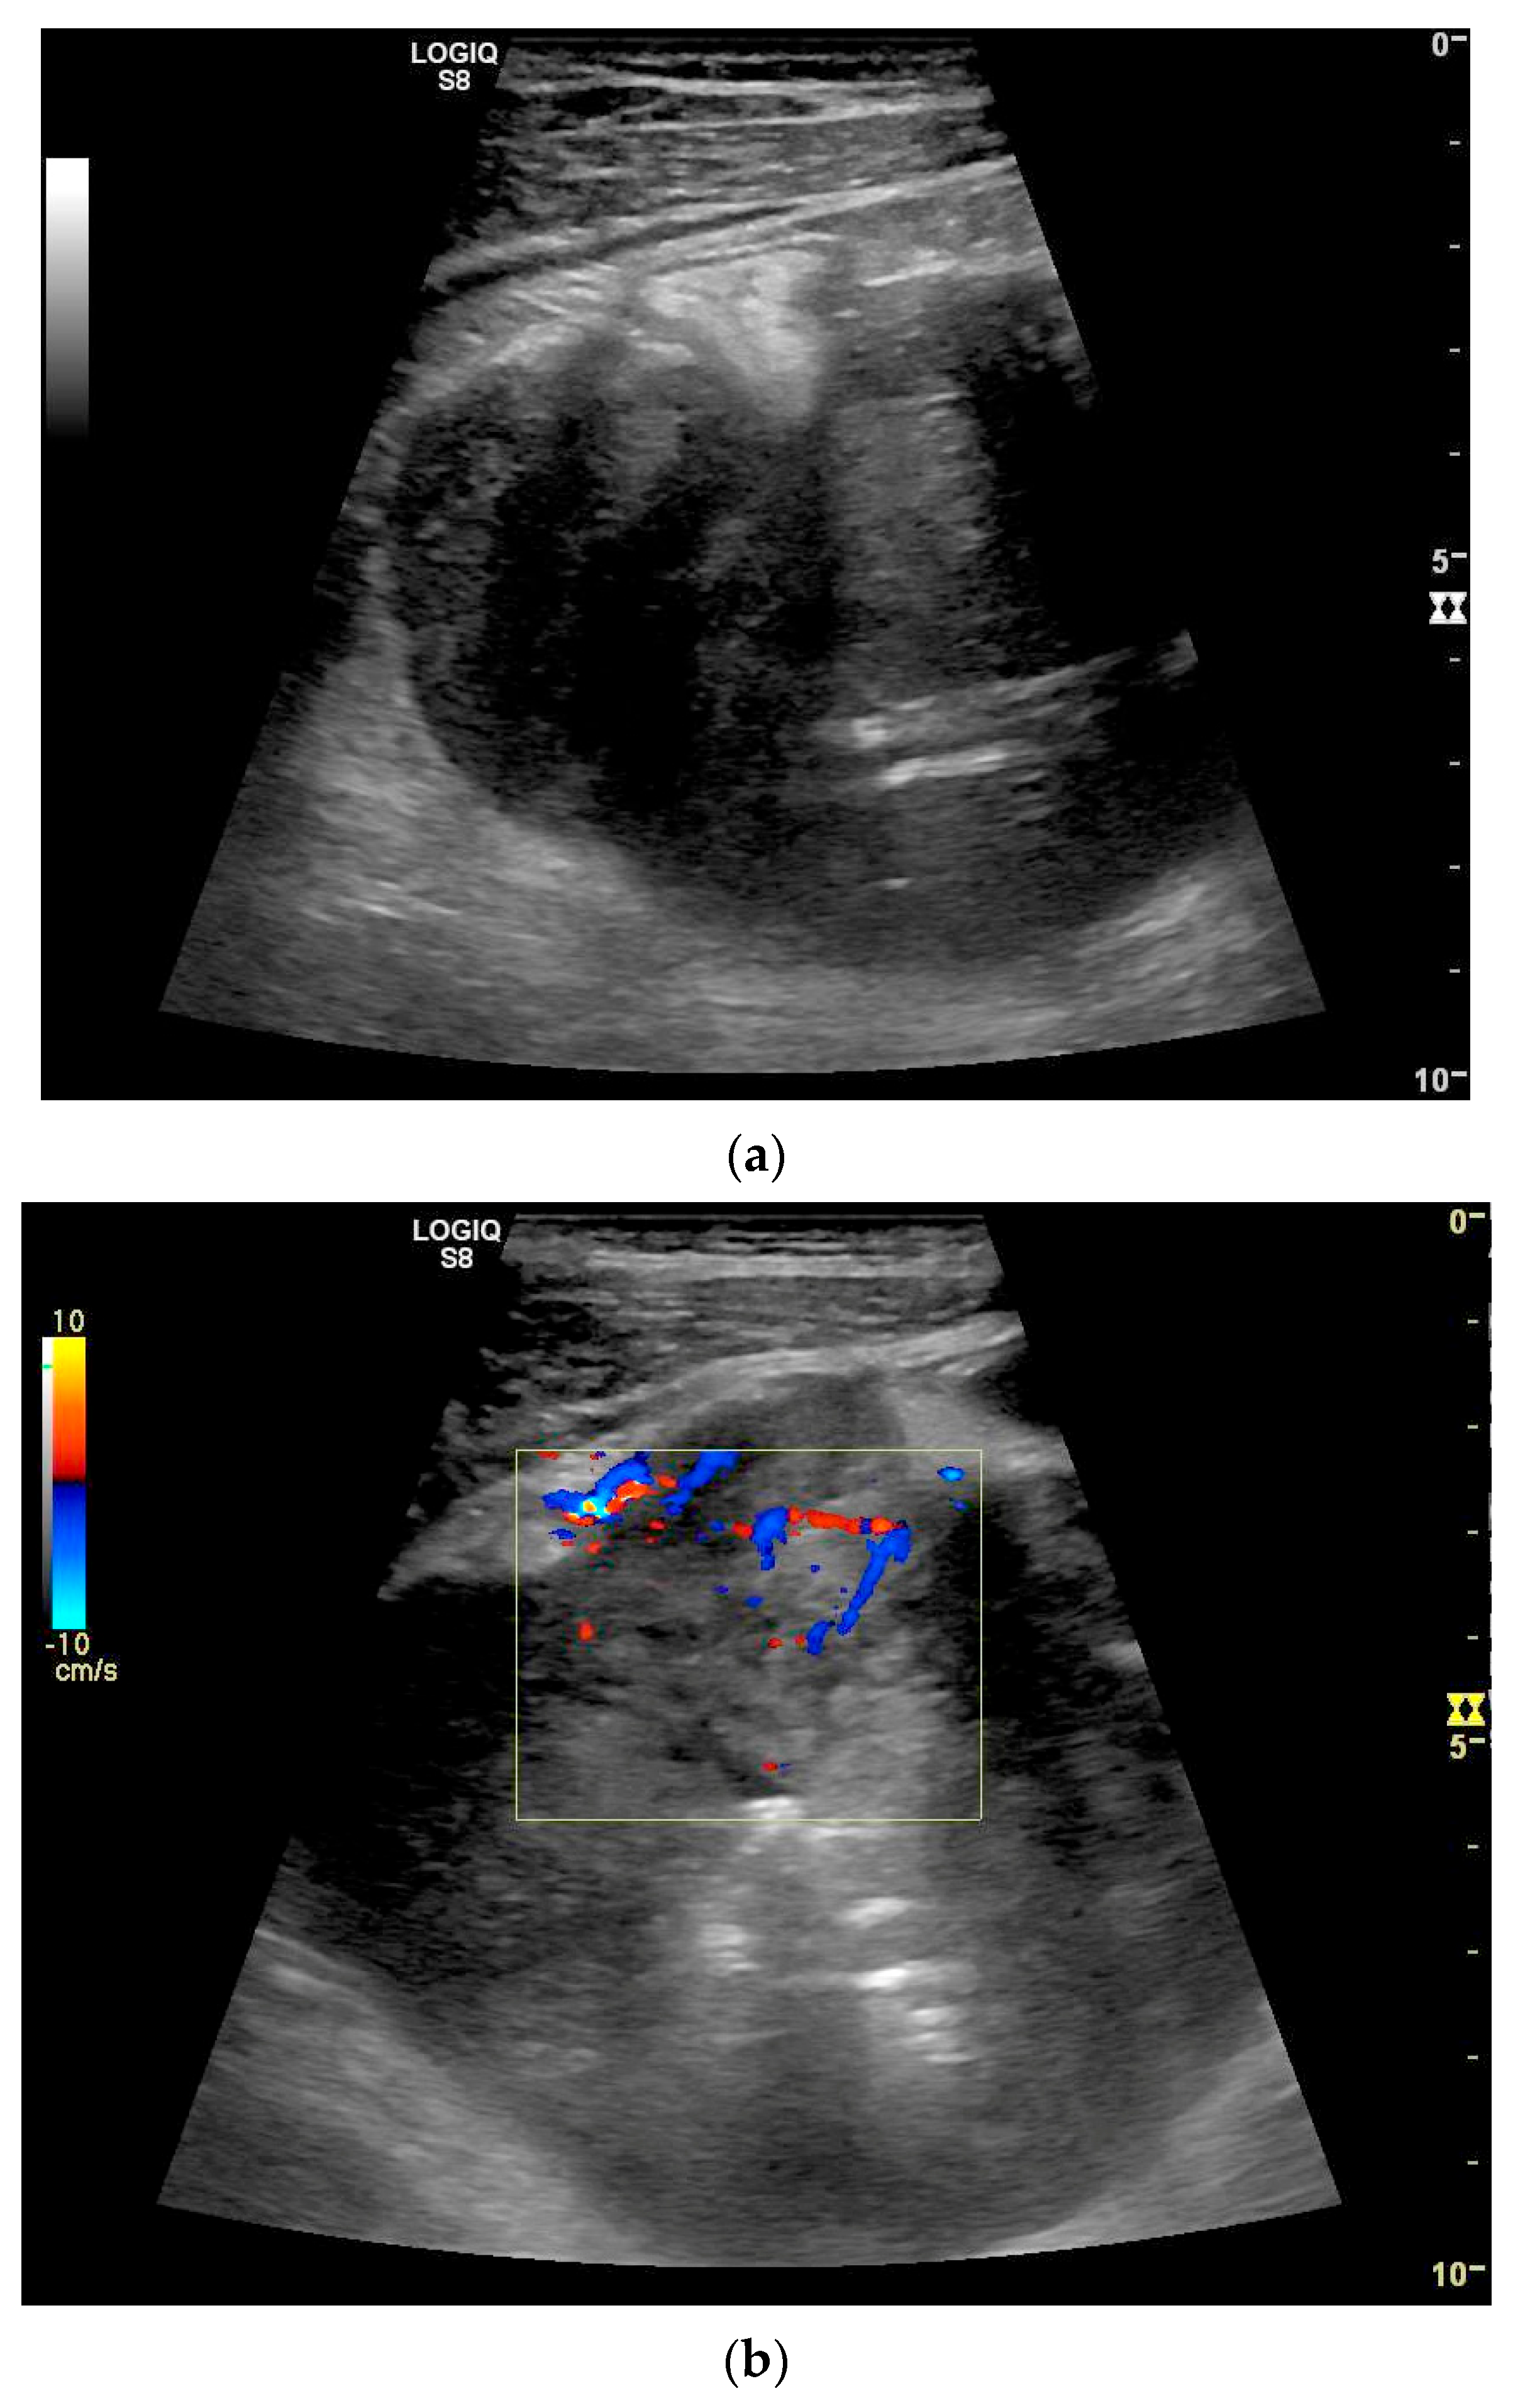

The only US description of an ileal IFP is as a clearly defined “target-like” lesion, which led to ileo-ileal intussusception [130] (Figure 13).

Figure 13.

Inflammatory fibroid tumor (Vanek’s tumor). In cases of unclear occult gastrointestinal bleeding, a smooth-edged oval hypoechoic mass measuring up to 30 mm in size can be seen in the terminal ileum. Examination with the abdominal sector transducer 1–5 MHz (a) and linear transducer 2–9 MHz (b). In power Doppler, a feeding vessel (c) and macro vessels in the mass (d) are visible. In CEUS with 2.4 mL SonoVue using a 9 MHz linear transducer, hyperenhancement is only visible at the edge in the arterial phase. Few vascular signals are visible in the lesion (e). The tumor remains hypoenhanced (f).